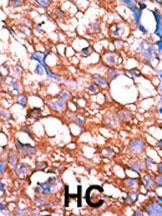

Formalin-fixed and paraffin-embedded human cancer tissue reacted with the primary antibody, which was peroxidase-conjugated to the secondary antibody, followed by AEC staining. This data demonstrates the use of this antibody for immunohistochemistry; clinical relevance has not been evaluated. BC = breast carcinoma; HC = hepatocarcinoma.